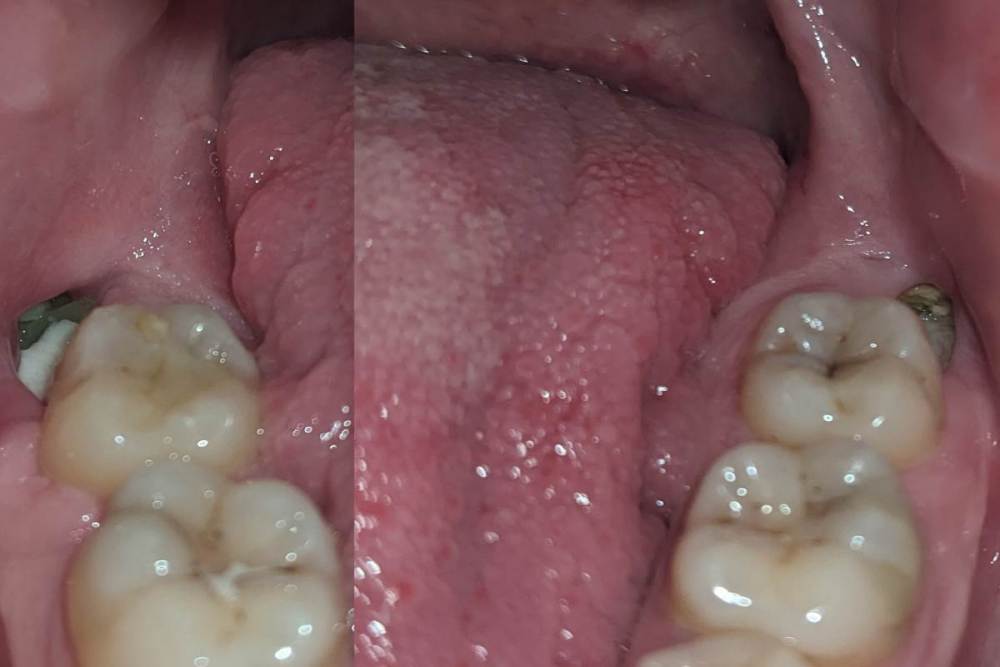

woogowoogi Опубликовано 1 декабря, 2023 Автор Поделиться Опубликовано 1 декабря, 2023 (изменено) 8 часов назад, Irouil сказал: Лучше всего сходит к леяащему врачу С очень высокой долей вероятности, достаточно просто промыть лунки антисептиком (из ирригатора на минимальном напоре либо из шприца с затупленой иглой), для пущей эффективности можно заложить в лунки Метрогила (из того же шприца, к примеру) и минут на 10 прикрыть их стерильными тампончиками, потом тщательно выполоскать рот водой Ничего криминального нет, но чистота лучше, чем не чистота Здравствуйте, вчера почистил щеткой лунки как смог, сегодня с утра начал поласкать рот средством с хлоргексидином, и мазать мазью Пародиум, теперь вот так выглядит, это нормально? сказали ещё надо антибиотики пропить, не знаю есть ли смысл? Изменено 1 декабря, 2023 пользователем woogowoogi Ссылка на комментарий

woogowoogi Опубликовано 1 декабря, 2023 Автор Поделиться Опубликовано 1 декабря, 2023 (изменено) Вот вроде ближе Изменено 1 декабря, 2023 пользователем woogowoogi Ссылка на комментарий

Irouil Опубликовано 1 декабря, 2023 Поделиться Опубликовано 1 декабря, 2023 На правой фотографии в лунке явно что-то лишнее. Надо вымыть струйно. Антибиотики без симптоматики я бы не рекомендовал 2 Ссылка на комментарий

woogowoogi Опубликовано 1 декабря, 2023 Автор Поделиться Опубликовано 1 декабря, 2023 вроде очистил, но ощущение что уже фибрин вычищать стал, или это забитая еда была, не могу понять, вообще нормально что уже как месяц прошел а лунки до сих пор такие ? 2 часа назад, Irouil сказал: На правой фотографии в лунке явно что-то лишнее. Надо вымыть струйно. Антибиотики без симптоматики я бы не рекомендовал Ссылка на комментарий

woogowoogi Опубликовано 2 декабря, 2023 Автор Поделиться Опубликовано 2 декабря, 2023 17 часов назад, Irouil сказал: Вычищать не надо. Завели иглу в углубление, сильно надавили на поршень - все плохое вымоется, все хорошее - останется. Может быть немного больно Они долго заживают в таком состоянии, по несколько месяцев Здравствуйте, я думаю что теперь у меня просто фибрин, не так ли ? его не трогать ? 7 часов назад, Mailze сказал: Пожалуйста, не занимайтесь самолечением?. Голосую за осмотр врача хирурга, который проводил операцию удаления зубов. Он и вымоет лишнее и проконтролирует что ничего лишнего в лунке нет и лекарство положит при необходимости. Здравствуйте, подскажите пожалуйста, это фибрин на шрамах ? 18 часов назад, Raystom сказал: @woogowoogi можете купить шприц обыкновенный для вв инъекций 5 или 10 мл, набрать туда хлоргексидин 0.05%, подогнуть иглу и, глядя на себя в зеркало, направить иглу в лунку, и аккуратно нажать на поршень. Тем самым вы струйно промоете лунки. После этого вынимаете поршень из шприца и вносите внутрь немного метрогила, фиксируете поршень обратно и в уже "чистые" лунки так же как и хлоргексидин вносите метрогил. Постоянно мыть лунки так же крайне не советую. Есть запах и боль - моем, нет, то и нечего трогать. Но как было написано выше лучше сходить на осмотр. Здравствуйте, это же фибрин в лунках начал образоваться? Ссылка на комментарий